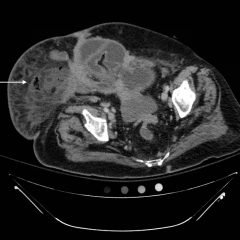

The initial CT scan found pneumomediastinum, which prompted a thoracic CT scan with contrast to determine the etiology and extent of the condition in the patient. The results of the scan prompted the treating ED physicians to consider esophageal perforation. Following consultation, the surgical and GI physicians did not recommend engaging acute intervention. Laboratory evaluation demonstrated mild hypokalemia and hyponatremia, both of which were addressed by administering intravenous (IV) fluids.

The thoracic CT scans showed extensive pneumomediastinum that tracked into the soft tissues of the neck, which given the history of vomiting also raised concern for esophageal perforation. There was still no evidence of mediastinal abscess or fat stranding. Additionally, a left subclavian vein port catheter, which terminates with tip at the cavoatrial junction of the superior vena cava can also be seen on the image.